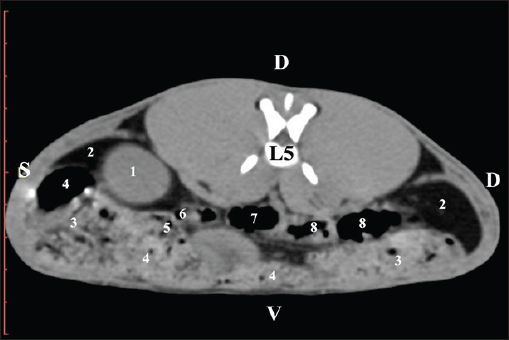

Fig. 11. Pre-contrast computed tomography (CT) anatomical scan of the regio-abdominis media at the caudal L4 edge level. (1) Ren sinister; (2) pelvis renalis; (3) ureter; (4) adipose collections; (5) cecum; (6) colon ascendens; (7) colon transversum; (8) colon descendens; (9) mesenterium; (white arrows) recessus renalis; (*) crista renalis. The L5 scan revealed the caudal end of the left kidney. It was adjacent to some small intestinal segments, including the duodenal pars ascendens, ileum, cecum, and colon ascendens (Figs. 12 and 13).

Fig. 12. Pre-contrast computed tomography (CT) anatomical scan of the regio-abdominis media at the cranial L5 edge level. (1) Ren sinister; (2) adipose collections; (3) cecum; (4) colon ascendens; (5) jejunum; (6) pars ascendens of the duodenum; (7) colon transversum; (8) colon descendens.

Fig. 13. Pre-contrast computed tomography (CT) anatomical scan of the regio-abdominis media at the caudal L5 edge level. (1) Ren sinister; (2) adipose collections; (3) cecum; (4) colon ascendens; (5) colon transversum; (6) colon descendens. Post-contrast CT imagingCT anatomical study at the Th13 level was used to define the right kidney zones. The medulla renalis was found as a hyperattenuated soft tissue with peripheral linear and wavy margins that reached the relatively hypoattenuated renal cortex. The most peripheral structure was the capsula adiposa, characterized by hyperattenuated soft tissue and uniform relief. The hyperattenuated aorta abdominalis, v. cava caudalis, and a. renalis appeared medially to the right kidney (Fig. 14).